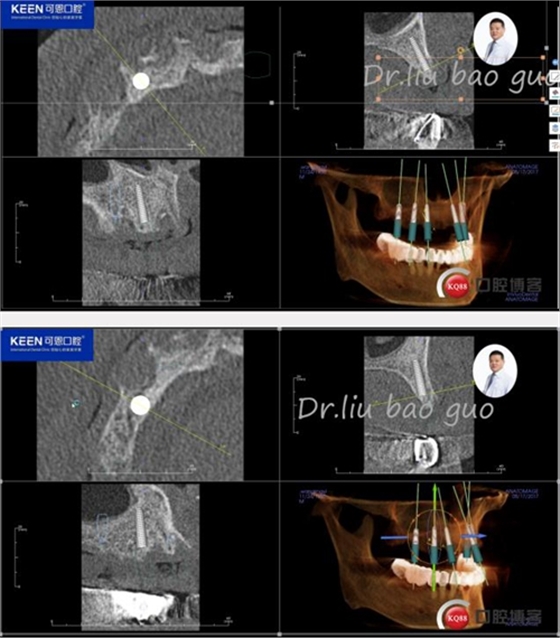

手術(shù)前種植軟件設(shè)計(jì)方案

數(shù)字化種植導(dǎo)板設(shè)計(jì)及制作

手術(shù)過(guò)程